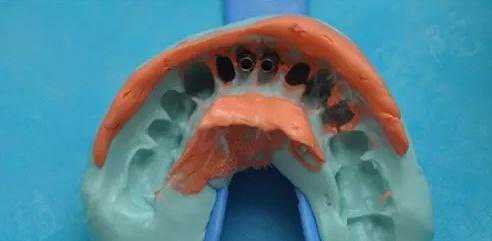

3,获取硅橡胶印模

隐形矫治治疗成功的第一步是需要获取一个好质量的印模,这样才能确保临床医生对牙齿解剖形态有清晰的认识,同时也可保证加工出最精准的隐形矫治器。

4,印模扫描

将获取的印模通过激光3D扫描和光栅式3D扫描相结合的方式对硅橡胶印模进行扫描分析,获得三维数字牙颌模型。